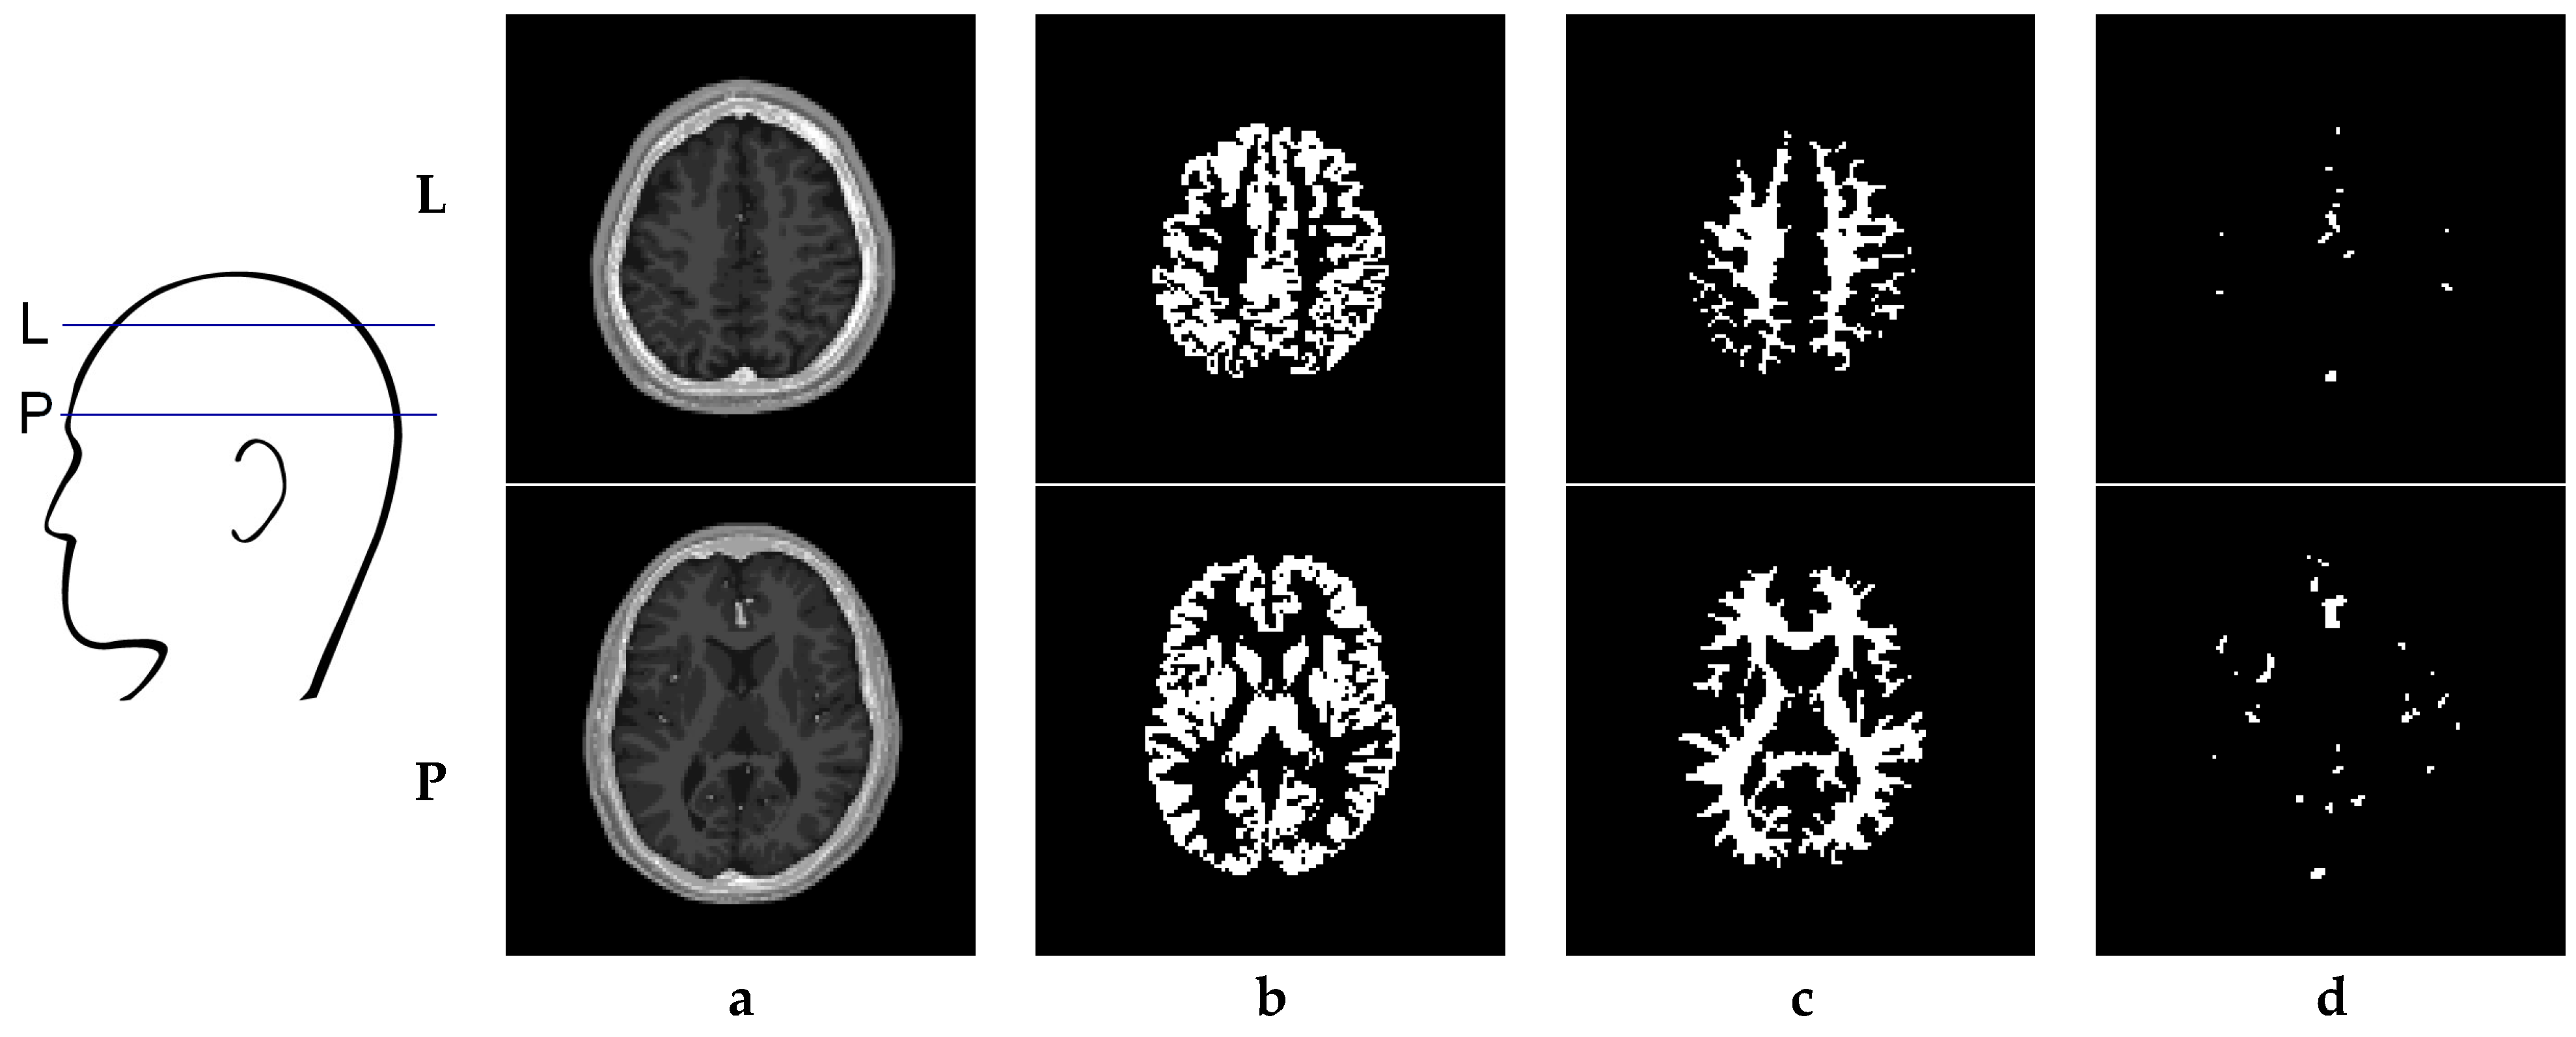

6. Creation of DSC-MRI Measurement Curves and a Brain Anatomy Model

- Kalicka, R.; Lipiński, S. A fast method of separation of the noisy background from the head-cross section in the sequence of MRI scans. Biocybern. Biomed. Eng. 2010, 30, 15–27. [Google Scholar]